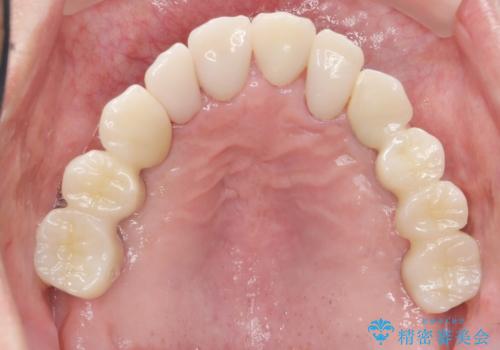

しっかりと咬むことができるようになり、喜んで頂けました。

他院ではお断りされたインプラント治療を行うことができ、ご満足頂けました。

インプラントの種類:ストローマン BLT

被せ物の種類:オールセラミッククラウン ベレッツァ